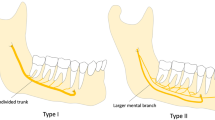

As main trunk of the IAN, the trigeminal nerve emerges as the fifth cranial nerve from the lateral surface of the pons in both a motor and a sensory root. Subsequently, the sensory root expands into the trigeminal ganglion, from which three divisions of the nerve arise. As one of these, the mandibular nerve passes through the foramen ovale to the infratemporal fossa, wherein subsequently different branches are sprouted. One of them is the IAN, which enters the lower jaw as a sensible nerve at the mandibular foramen and runs in company with the mandibular vessels in the mandibular canal anteriorly, gradually crossing from a lingual to a more buccal plane. It supplies the mandibular teeth with sensory branches that form into the inferior dental plexus and give off small dental nerves to the teeth [1].

The cranio-caudal and bucco-lingual positions, as also the branching pattern of the neurovascular bundle, differ within the mandibular body when different mandibles are compared. At the mental foramen, the nerve leaves the corpus mandibula mostly after a short recurrent intra-osseous course, creating the so-called anterior loop [9]. The shape, curve, and direction of this terminal segment are quite variable. Before the nerve leaves the corpus mandibula, it gives birth to a small branch as the continuation of the inferior alveolar nerve, which prolongs its course inside the mandible and innervates the mandibular canines and incisors.

Variations of the mandibular canal, such as BMC, are reported with incidences ranging from 0.08% to 65.0% [3, 5, 7, 19, 20] (Table 1). The first-mentioned TMC was only based on a conventional optical projection tomography (OPT3), however, not confirmed by CBCT. Causes for misinterpretation underlying a false double-canal radiograph using a conventional OPT may include the imprint of the mylohyoid nerve on the internal mandibular surface, where it separates from the inferior alveolar nerve and travels to the floor of the mouth. Another explanation is the radiologic osteocondensation image produced by the insertion of the mylohyoid muscle into the internal mandibular surface, with a distribution parallel to the dental canal [15, 26]. The first established case of a TMC was presented in a study on dry mandibles [5].